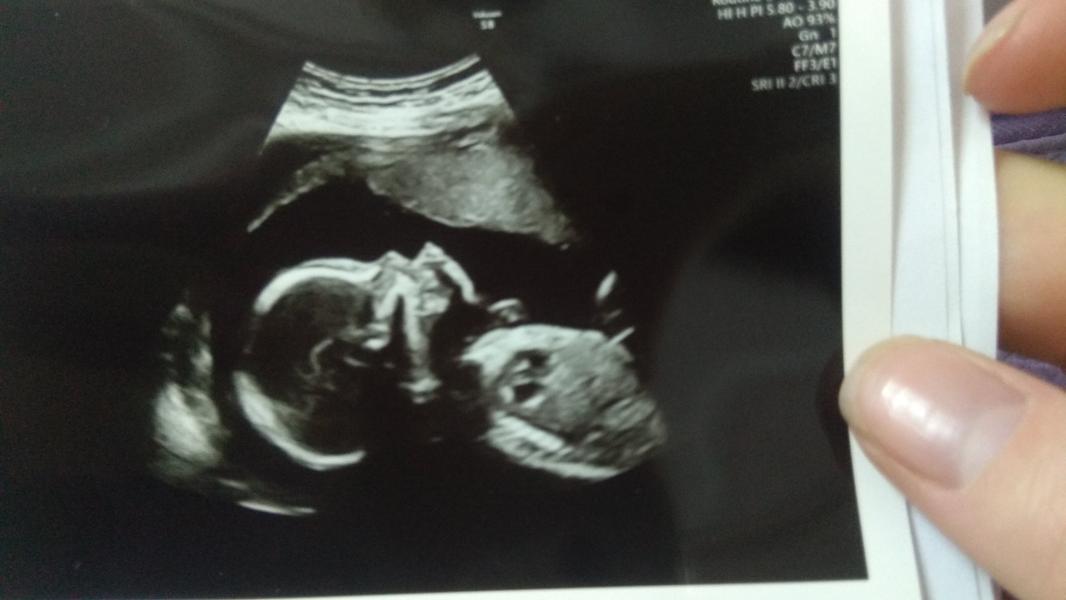

Прошли 2 скрининг! Все хорошо, развиваемся согласно сроку) ну и у нас будет мальчик, хотя все так ждали девочку)) но нет мальчуган растёт))) Если честно что то так волновалась перед скринингом, а опять поняла что только сама себя накручиваю((( Вылезла просто простуда на губе, переморозилась когда гуляла. Ну нет же все прочитала что это не страшно, не стоит переживать. Но в глубине души все равно переживала пока не увидела свою кроху на мониторе)) Ещё так интересно с утра сдавала кровь натощак а потом сразу на скрининг, врач показывает засунул обе руки в рот и сосет пальцы, она мне вы что ребенка не кормите))) и второй раз показывают пенис, я все равно ничего не понимаю в этом крошечном состоянии)) только киваю да да вижу)))